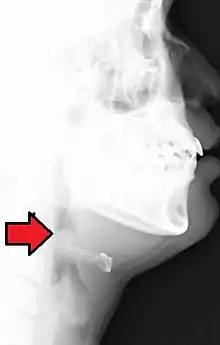

Lateral radiograph showing the "thumb sign". The diagnosis of epiglottitis was confirmed on subsequent imaging and laryngoscopy. The patient recovered following treatment with prednisone and ceftriaxone

In a lateral C-spine radiograph, the sign is caused by a thickened free edge of the epiglottis, which causes it to appear more radiopaque than normal, resembling the distal thumb.